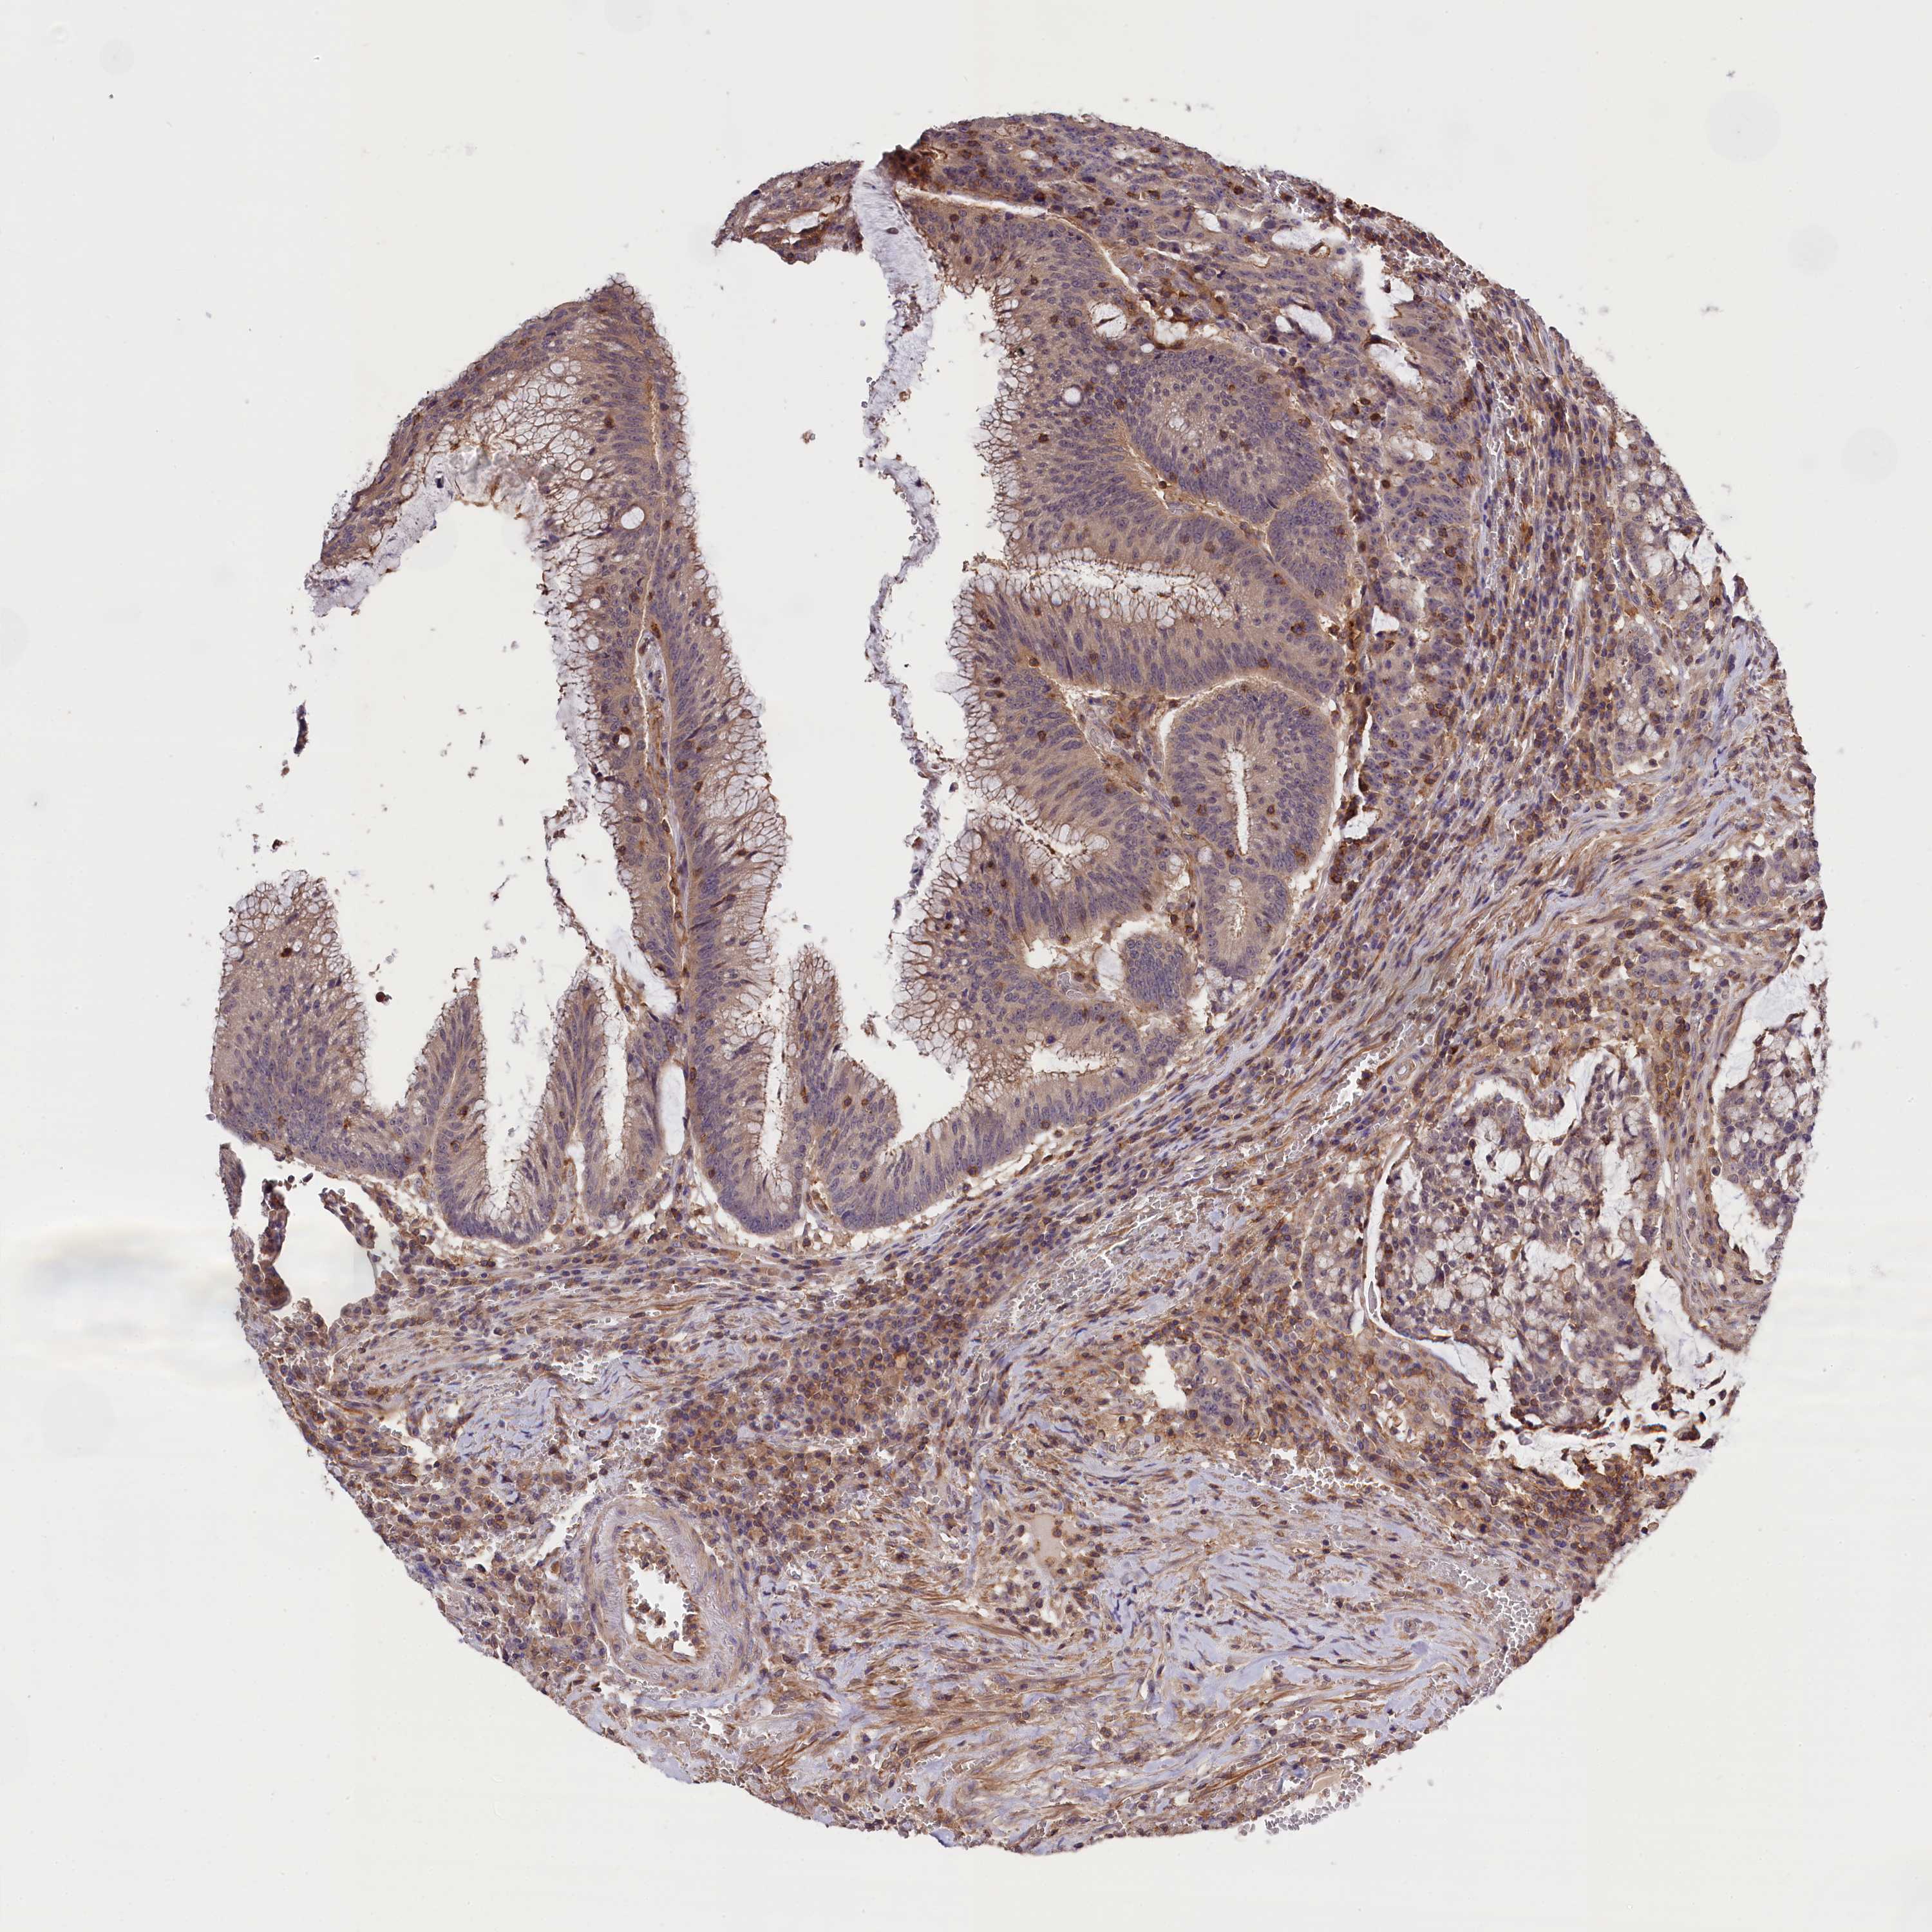

CANCER COLORECTAL CANCER Show tissue menu

Colorectal cancer

Human cancer

Colon adenocarcinoma